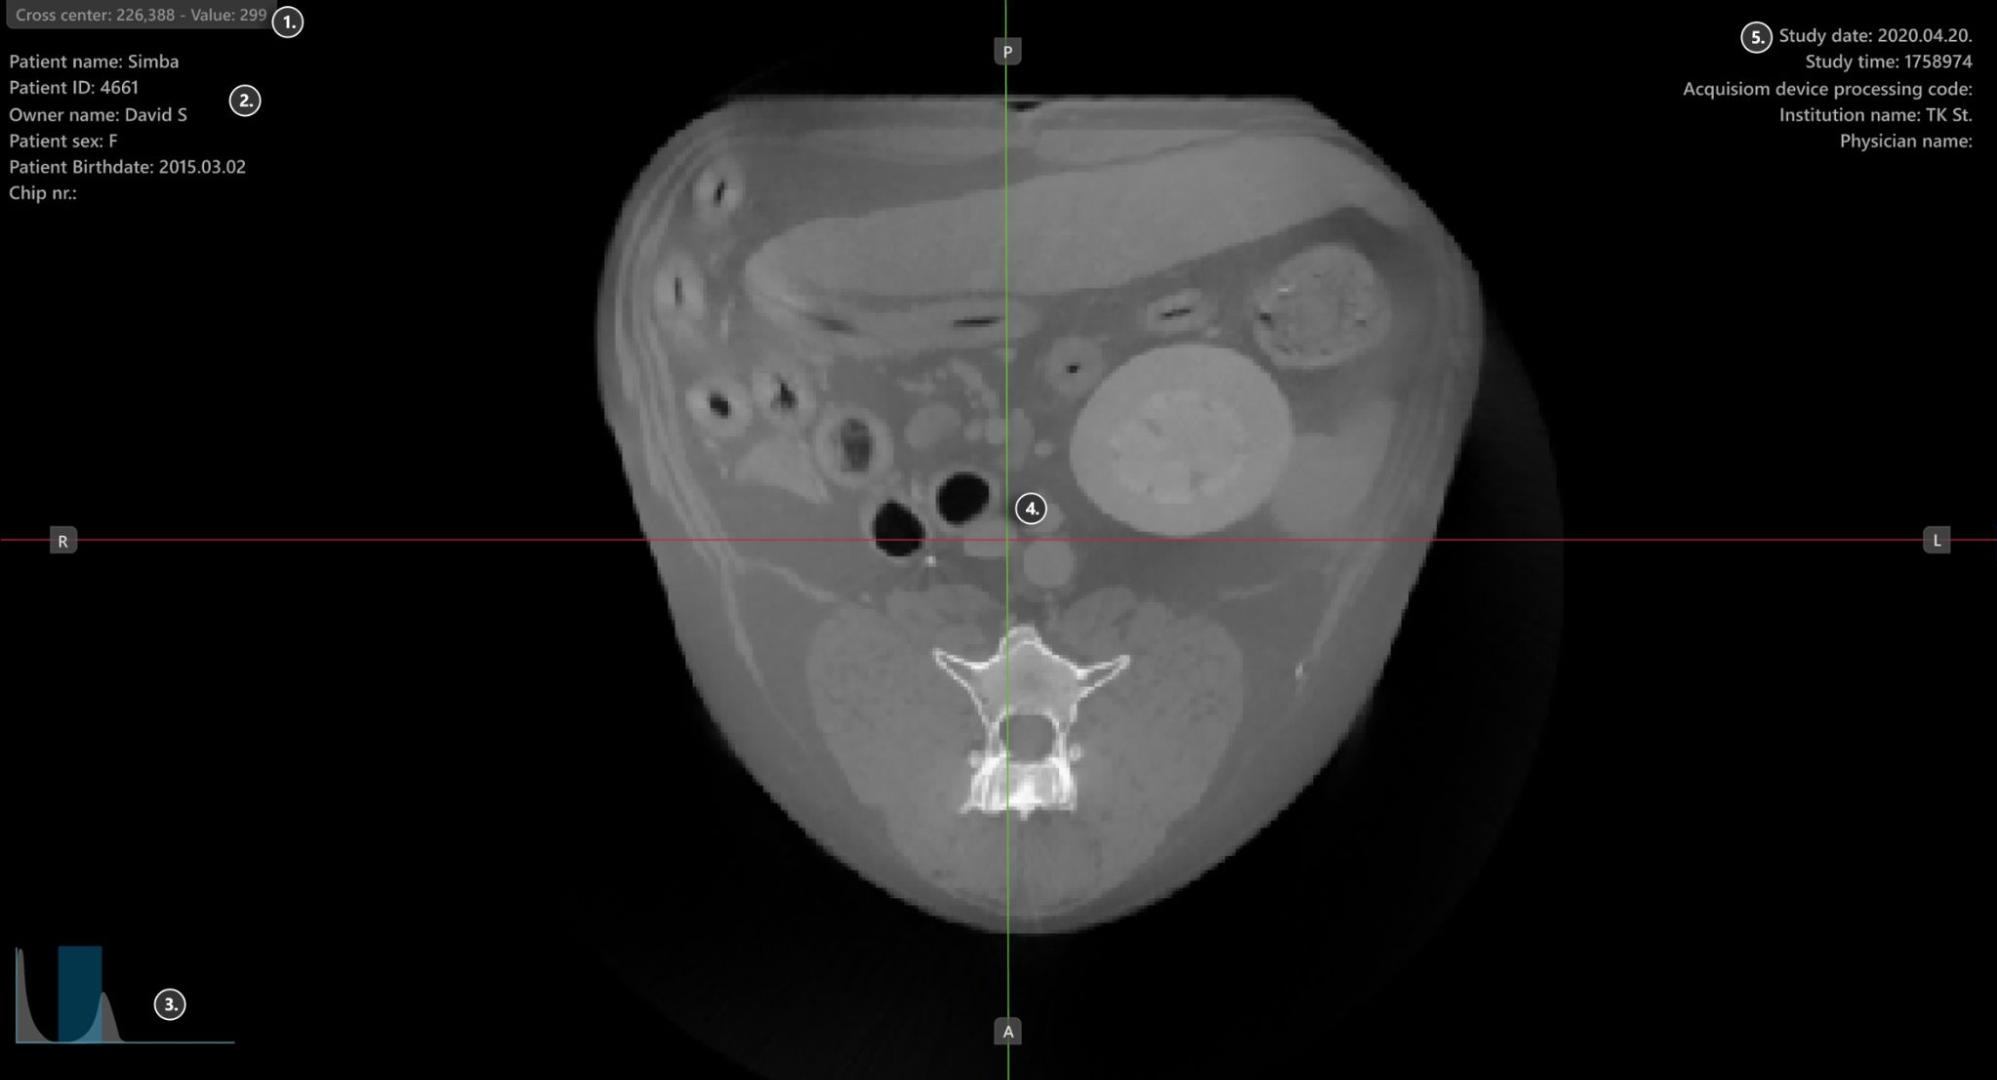

Sections of the VisioVIEW CT Viewer¶

The VisioVIEW CT Viewer consists of several sections, each tailored to a specific purpose. Below is a detailed description of each section.

Viewer Area¶

HU (Hounsfield Unit) pixel value

Patient information

Windowing histogram tool

Slicers

Study information